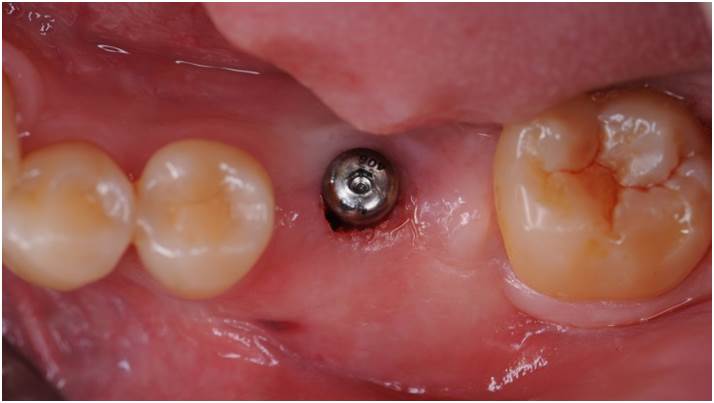

“AnyOne implant system guarantees

excellent aesthetics & functionality for any implantologist

& any patient. ”

Clinical case: Single molar implant with bone augmentation

- Courtesy of Dr. Jung Sam Lee, Korea -

Keywords

AnyOne, bone augmentation, osteotomy socket, peri-implant tissue, autogenous bone, GBR, single replacement, Auto-Max, Dr. Jung Sam Lee

Products:

AnyOne implant system, Auto-Max